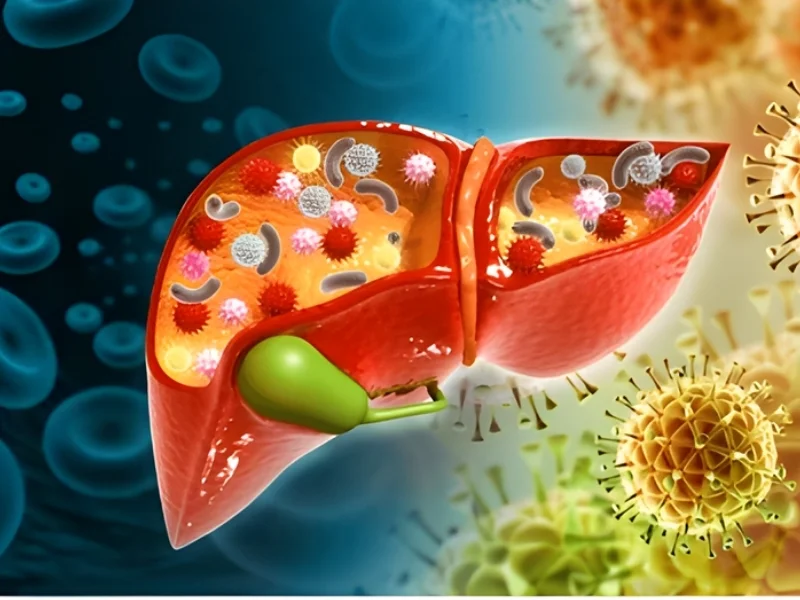

Risk Factors For Liver & Bile Duct Cancer

Hepatitis B or C infection

Chronic liver disease or cirrhosis

Bile duct inflammation or abnormalities

Excessive Alcohol Consumption

Liver parasites or infections

Primary Sclerosing Cholangitis